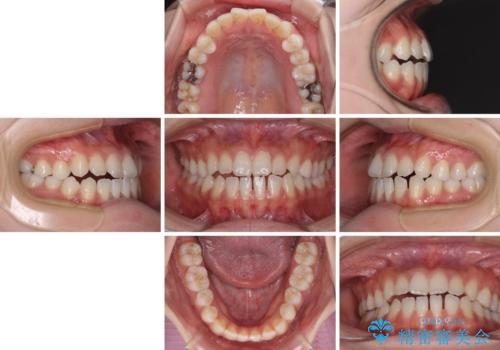

舌突出癖で口元が開いてしまう 舌トレーニングを行ったインビザライン矯正

- 前歯の上下スペースと前歯の隙間を気にして来院された患者様です。

インビザラインにより上下の前歯の隙間を閉じていくこととしました。

上下の隙間に舌が入り込むことが、すきっ歯やオープンバイトの原因であったため、舌の筋肉のトレーニングも並行して行い、後戻りの抑制を図りました。